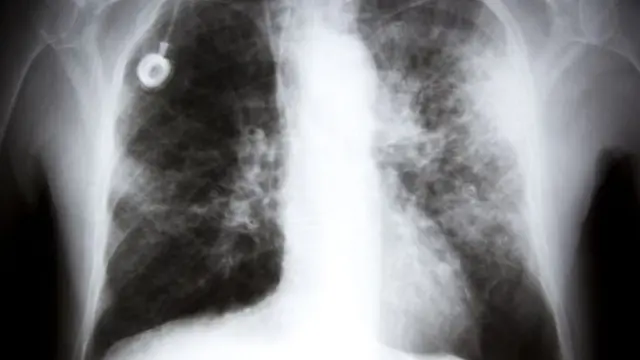

عادة ما تصنف الأورام السرطانية وتعالج وفقا للمكان الذي ظهرت فيه بالجسم لأول مرة، مثل سرطان الثدي أو الرئة.

كما توصلت إلى أن أنواعا شائعة من السرطان، مثل سرطان الرئة والثدي، يمكن تصنيفها إلى أكثر من نوع واحد من السرطان.

وقال بينز إن سرطان الرئة والقولون هو من بين تلك الأنواع التي يمكن أن تستفيد من وسائل العلاج الأكثر دقة.